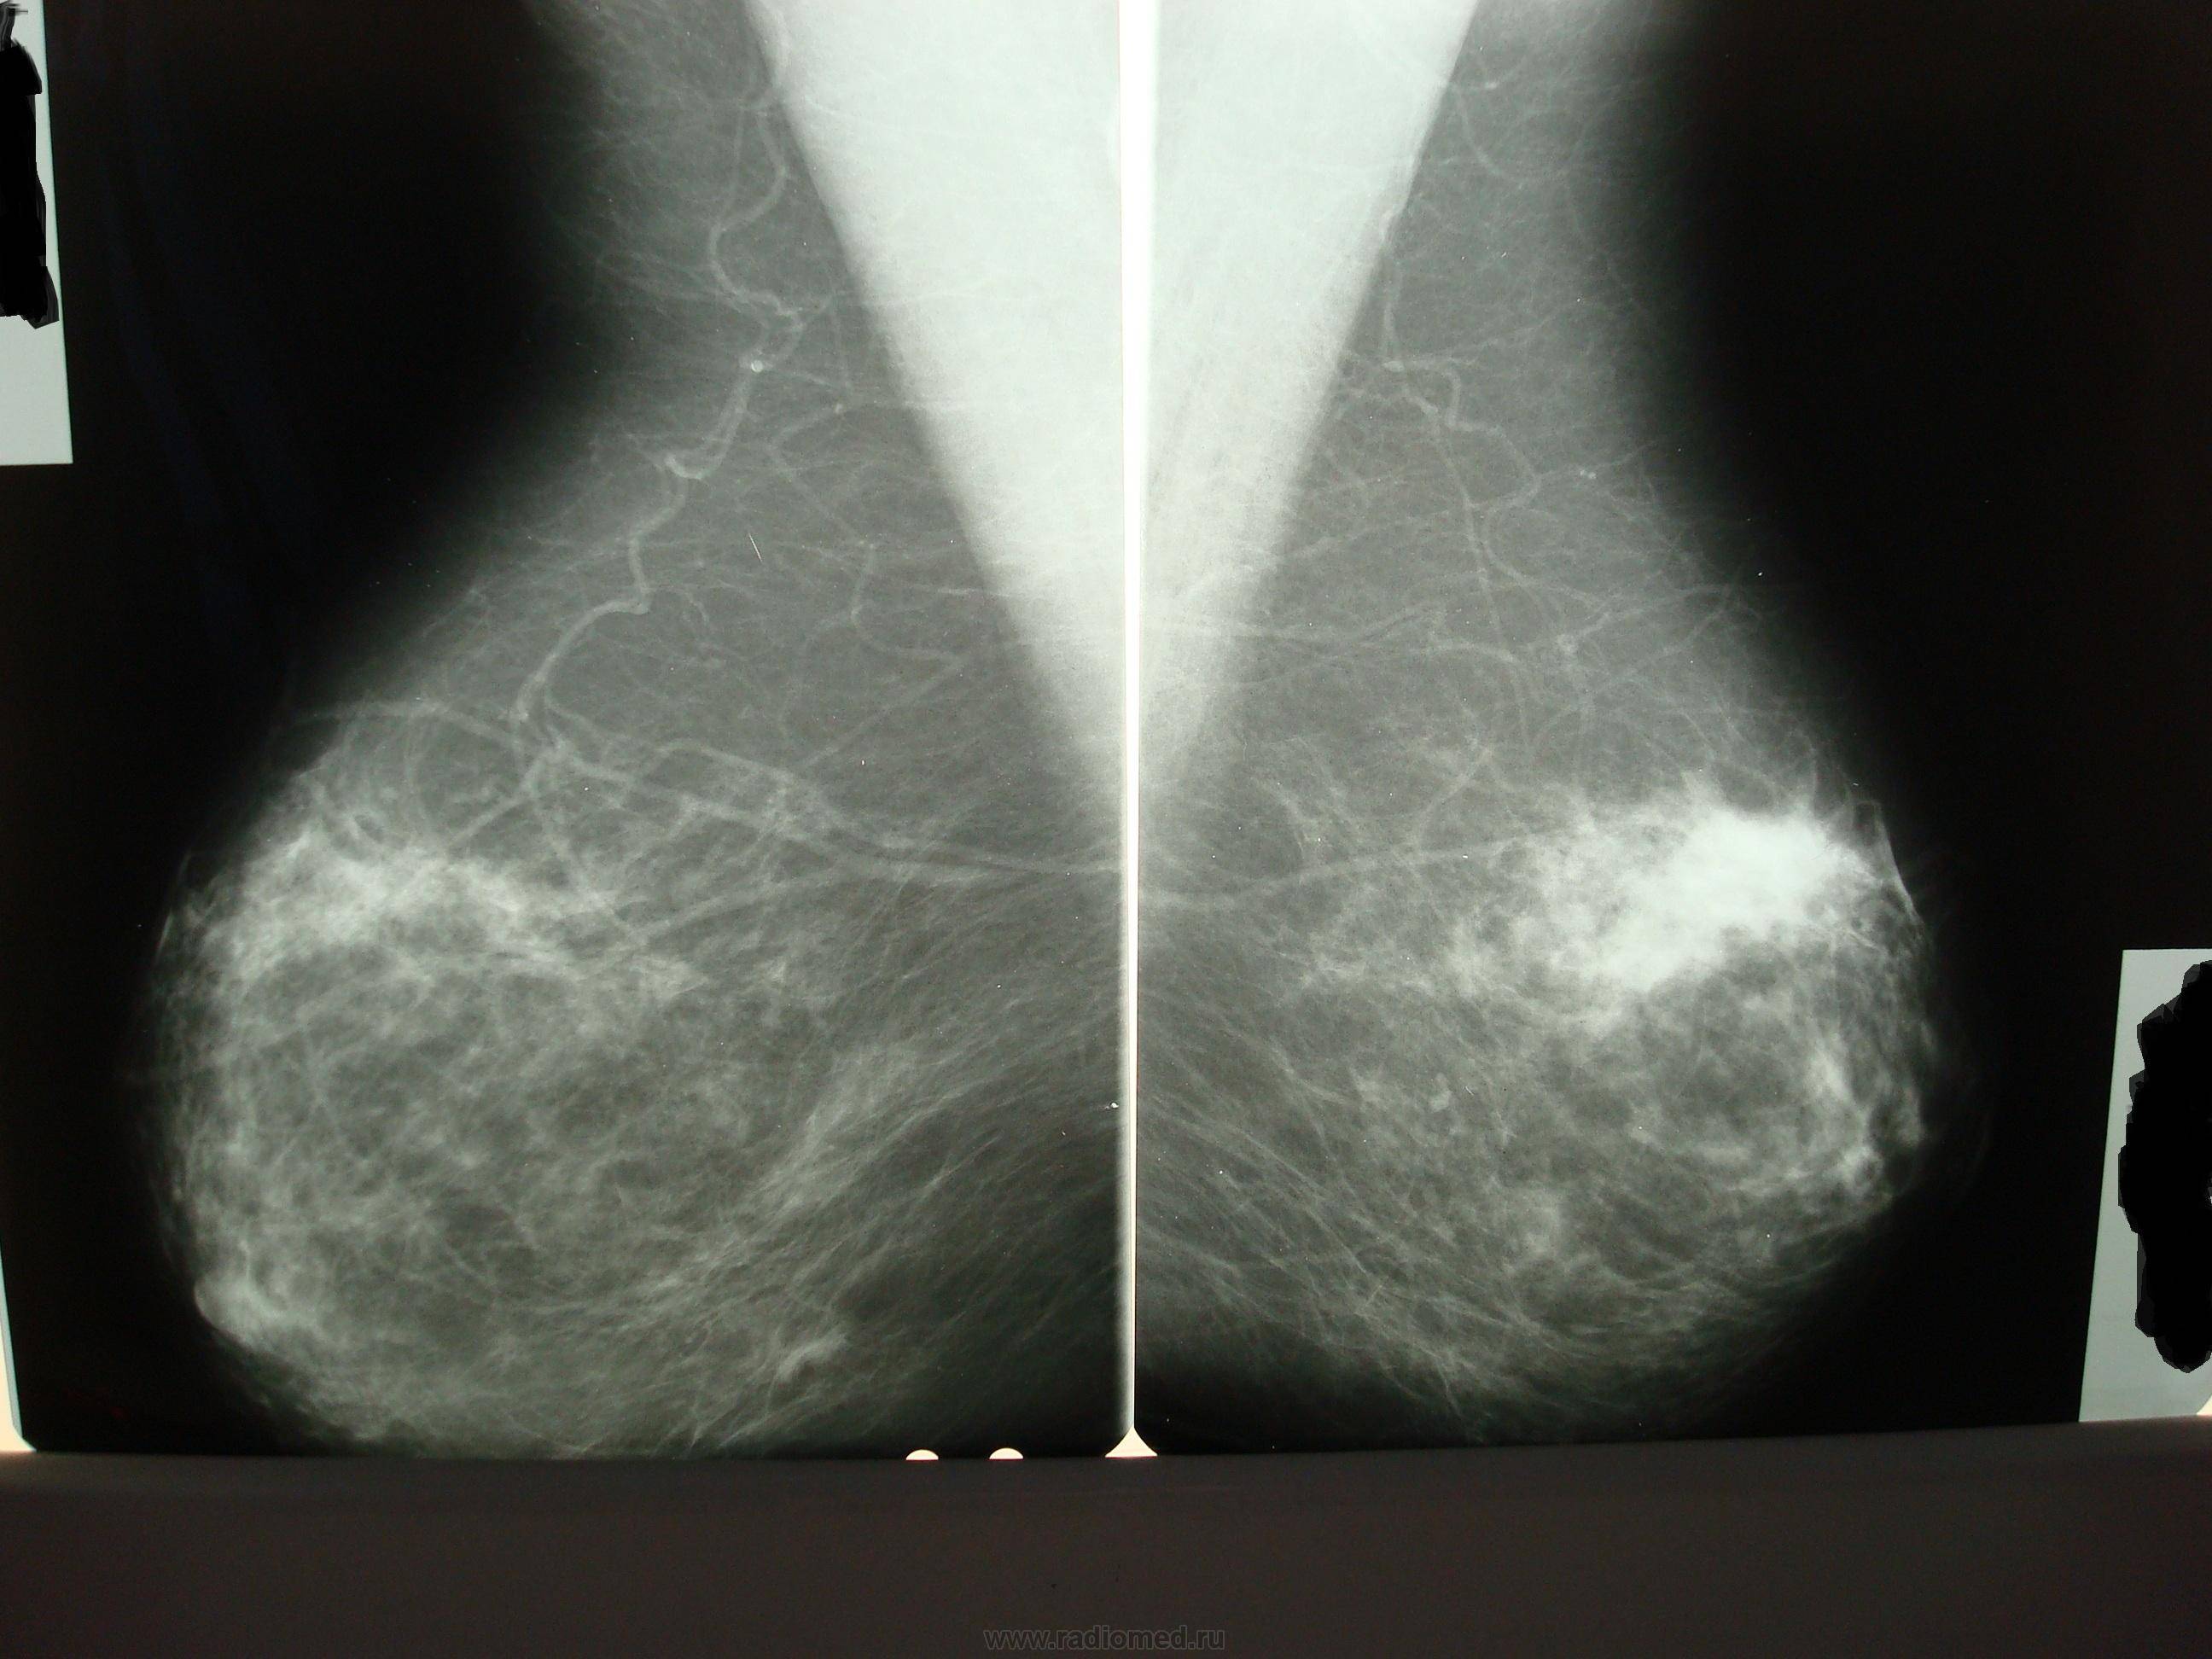

Фиброаденома молочной железы - доброкачественное образование, которое часто встречается у женщин. Оно может быть обнаружено при помощи различных методов диагностики, включая маммографию. Ниже представлены фотографии, помогающие понять, как выглядит данное заболевание.

Фиброзно-кистозная мастопатия рентген молочных желез

Фиброзно кистозная мастопатия маммограмма

Маммография и ее роль в диагностике фиброаденомы молочной железы

Маммография - это рентгенологическое исследование молочных желез. Оно позволяет выявить различные изменения в тканях, включая фиброаденому. На маммограммах можно увидеть структурные особенности опухоли и отследить ее динамику во времени.